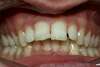

Appareillage